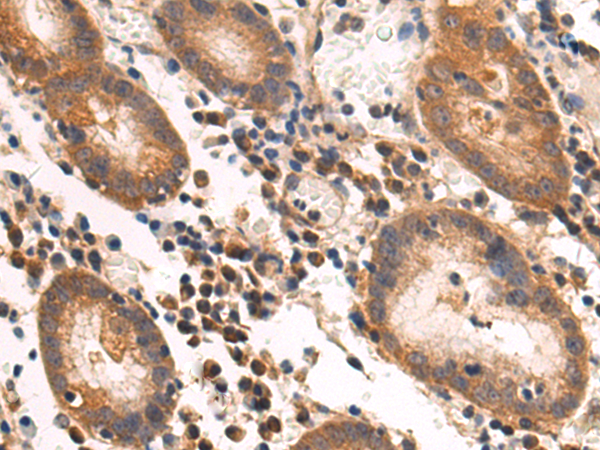

分类: 科研抗体货号: P03662别名: CHIP; SCA48; UBOX1; SCAR16; HSPABP2; NY-CO-7; SDCCAG7应用: WB,IHC反应种属: Human, Mouse